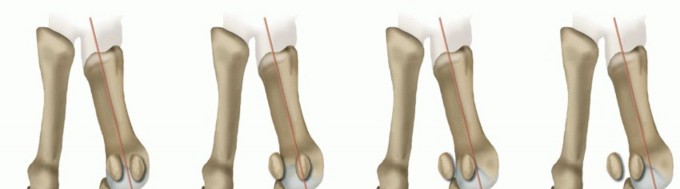

Congruent first MTP joint (physiologic distal metatarsal articular angle [DMAA])

The literature suggests that that lateral deviation of the great toe is the primary event leading to hallux valgus deformity. This primary deforming force has a reciprocal relationship with metatarsus primus varus; the first and second intermetatarsal angle (IMA) worsens with an increase in the hallux valgus angle (HVA)

and vice versa.10,20 The valgus of the proximal phalanx produces forces whose vectors determine the lateral deviation of the head of the first metatarsal.4,6,10,12

Congruent first MTP joint (increased DMAA)

With an increased DMAA, hallux valgus is present despite congruency of the first MTP joint. The articular surface of the first metatarsal head is in a valgus position relative to the first metatarsal shaft axis; therefore,

hallux valgus is present even without an imbalance of the muscle forces on the first MTP joint.12 However, this imbalance leads to a worsening of the deformity. Hallux valgus with an increased DMAA is less common than the incongruent type and typically occurs in men and younger patients (juvenile hallux valgus).3,4,5,6,7

The HVA is determined by the intersection of the diaphyseal axes of the first metatarsal and the proximal phalanx. Arbitrarily, a normal HVA does not exceed 15 degrees (FIG 1A).

The IMA is the angle between the diaphyseal axes of the first and second metatarsals. Arbitrarily, a normal IMA does not exceed 9 degrees (FIG 1B).

FIG 1 • AP radiograph of a patient with hallux valgus. Left, HVA (up to 15 degrees). Second from left, first IMA (up to 9 degrees). Second from right, sesamoid position. In this patient, the tibial sesamoid is divided into two halves by the diaphyseal axis of the first metatarsal, which means the beginning of a grade 2

sesamoid subluxation (normal is grade 0). Right, relative length of the first and second metatarsals; normal is up to 5 mm.

FIG 2 • Evaluation of hallucal sesamoid position. Grade 0, no displacement of sesamoids relative to the middle diaphyseal axis of the first metatarsal (normal). Grade 1, overlap of less than 50% of the tibial (medial) sesamoid to the reference line. Grade 2, overlap of more than 50% of the tibial sesamoid to the reference line. Grade 3, tibial sesamoid completely displaced beyond the reference line.